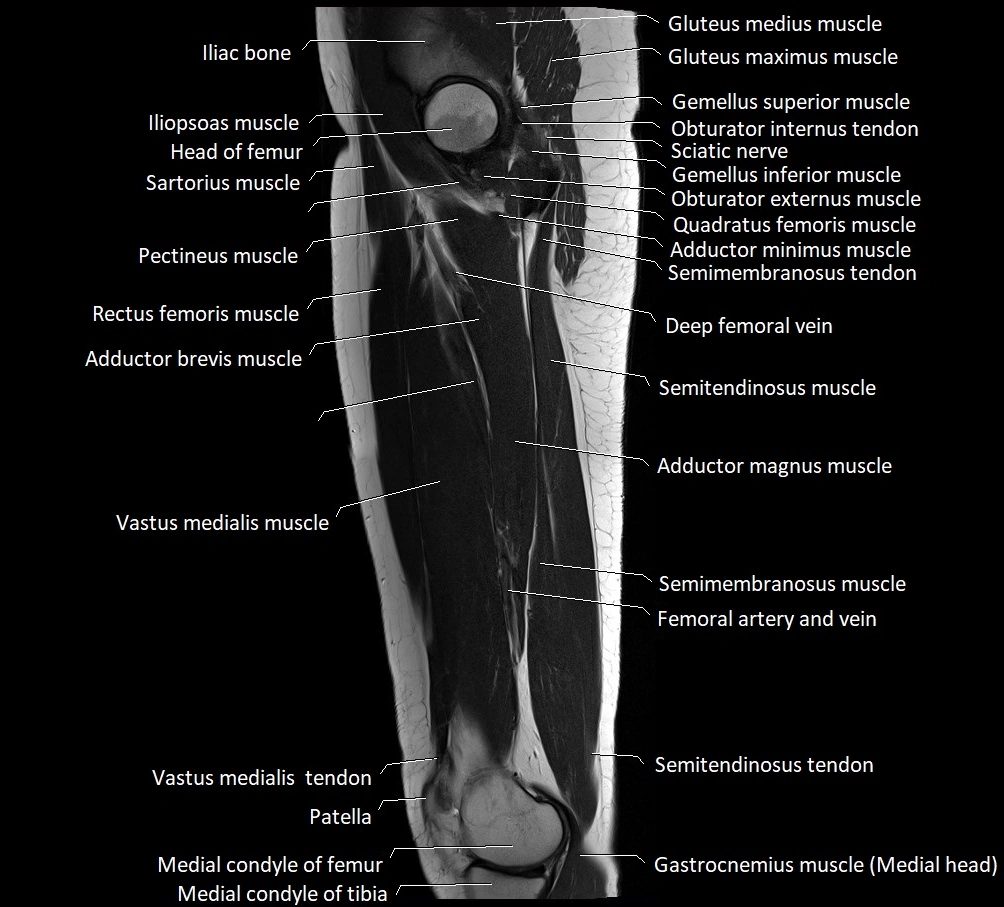

- Head of femur

- Iliopsoas muscle

- Ilium bone

- Inferior gemellus muscle

- Inferior gluteal artery

- Obturator externus muscle

- Pectineus muscle

- Quadratus femoris muscle

- Rectus femoris muscle

- Sartorius muscle

- Semimembranosus muscle

- Semitendinosus muscle

- Superior gemellus muscle

- Vastus medialis muscle